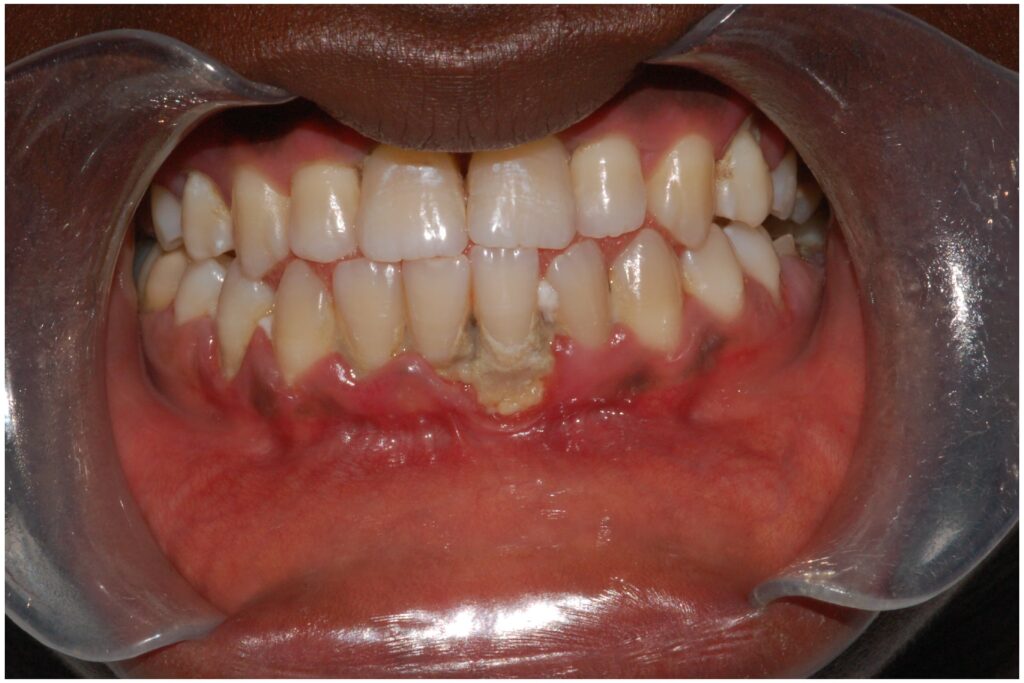

Ud over de umiddelbare symptomer kan kronisk, ubehandlet anæmi øge din risiko for at udvikle alvorlige og langvarige mundsygdomme. Den nedsatte iltforsyning til tandkødsvævet og et potentielt svækket immunsystem gør det sværere for kroppen at bekæmpe de bakterier, der forårsager tandkødsbetændelse (gingivitis) og paradentose. Paradentose er en alvorlig infektion, der nedbryder knoglen omkring tænderne og kan føre til tandtab. Hvis du har anæmi, kan din krops helingsevne også være nedsat, hvilket betyder, at tandkødsproblemer kan udvikle sig hurtigere og være sværere at behandle.

Samtidig er det ekstremt vigtigt at informere din tandlæge om din anæmi-diagnose. Din tandlæge skal kende til din tilstand for at kunne tage de nødvendige forholdsregler. Personer med anæmi kan have en øget risiko for infektioner efter tandbehandlinger, og nogle former for anæmi kan påvirke blodets evne til at størkne. Ved at kende din helbredsstatus kan din tandlæge skræddersy din behandling for at sikre, at den er så sikker og effektiv som muligt.